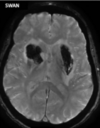

36

Which MRI sequences are used to identify haemorrhagic strokes, and what are the findings?

DWI SWAN: SWAN (susceptibility-weighted angiography) is highly sensitive for visualisation of blood vessels and blood products Haemorrhagic stoke findings: Hyperintense in hyperacute stage then becomes hypointense with hyperintense outer ring